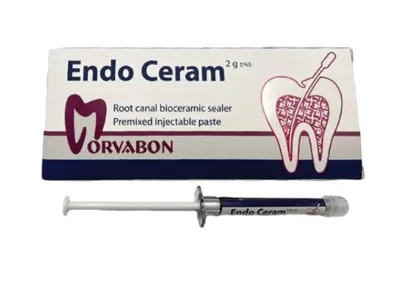

سیلر بایو سرامیک

شرکت/سازنده: MORVABON

کشور سازنده: ایران

برای اطلاع از قیمت محصول با شماره پشتیبان تماس حاصل فرمائید.

سیلر بایو سرامیک موقت

شرکت/سازنده: MORVABON

کشور سازنده: ایران

برای اطلاع از قیمت محصول با شماره پشتیبان تماس حاصل فرمائید.